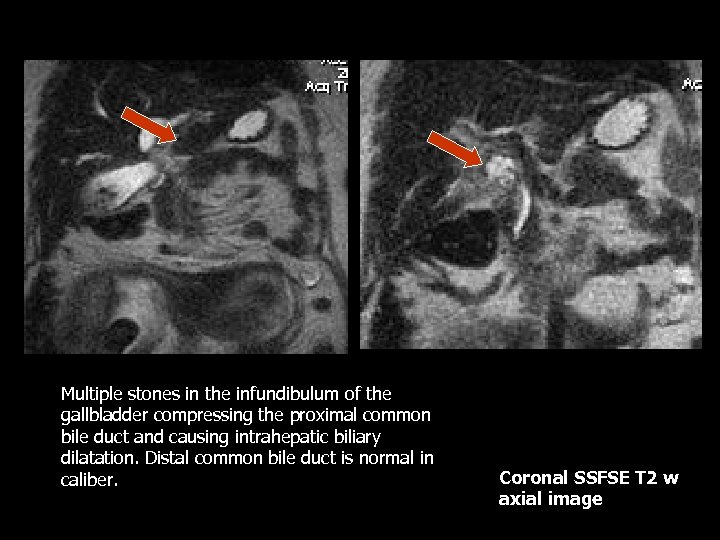

Multiple stones in the infundibulum of the gallbladder compressing the proximal common bile duct and causing intrahepatic biliary dilatation. Distal common bile duct is normal in caliber. Coronal SSFSE T 2 w axial image

Mirrizi Syndrome • Uncommon cause of obstructive jaundice that occurs in the setting of cholelithiasis and cholecystitis(10). • Obstruction of the CHD is caused by an impacted stone within the cystic duct(10). • Predisposing factors include low insertion of the cystic duct into the CHD. The cystic duct and the CHD travel in a sheath together before joining to become the CBD(10).